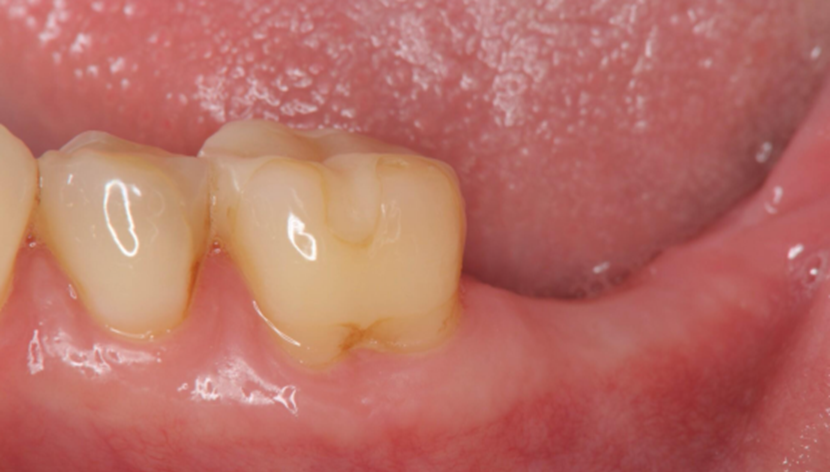

2. A follow-up examination was conducted three months after tooth extraction upon complete wound healing, and implant restoration was initiated.

Post-extraction wound healing status